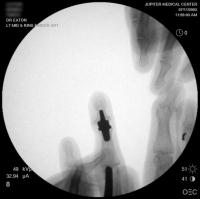

Intraoperative fluoroscopy.

Broach.

The trial implant sizer shows the true size of the implant. The final implant has a radiolucent coating  which makes it appear smaller than it is on Xray.